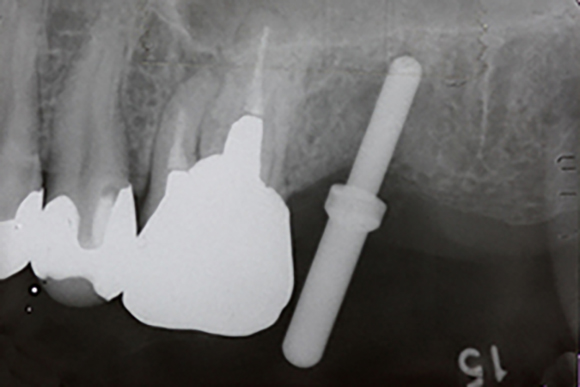

レントゲン写真

左上の一番後ろの奥歯がほとんどで虫歯で抜歯となりました。この部分に対してインプラントをしていくのですが、基本的に上顎には、下顎よりも長めのインプラントを埋入します。その際に上顎には上顎洞という空洞の部分があるのですが、ここには骨がありません。

抜歯後、上のレントゲンでは、右上の方に横に走る白い線が見えます。これが上顎洞の下底になります。そのため、ここに長めのインプラントを埋入すると上顎洞に触れる恐れがありますので、上顎洞の所にインプラントの埋入と同時に骨をつくるのが上顎洞挙上術です。

そこに対して、細い専用の道具でインプラントの入る通路を形成していきます。次のその先端部分から人工の骨を入れて行きます。

上のレントゲンの太い棒の先の部分に上顎洞の下底を貫通して白く顆粒上の物が写っているのが見えます。これが、人工骨を入れた部分になります。この分、インプラントが入るスペースが出来たので、ここに埋入していきます。

こののち6ヶ月ほど骨の成熟とインプラントと骨の結合を待ち、上の被せものを作って行きます。

今回使用したインプラントは、3iの新型インプラントのプリベールというもので、できるだけ周囲の骨が減少しにくくなるように設計されているインプラントです。